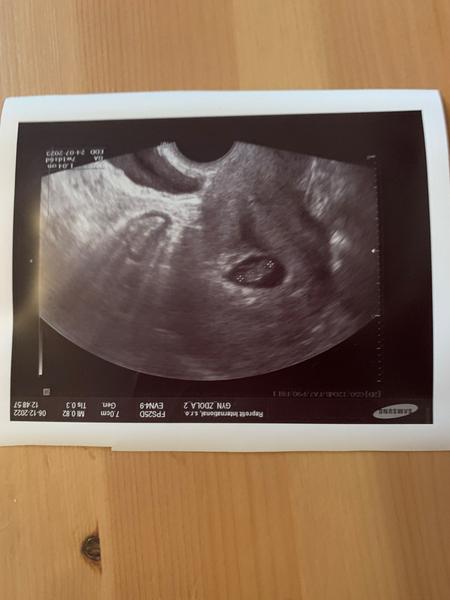

Ahoj holky, bohužel jsem musela na pohotovost, ale dobra zprava 6+3 a máme srdíčko❤️🙏🍀

Hlavně ze je vše v pořádku a skvělá zprava ohledně srdicka 🥰🥰

@kristynaprandl tak je všechno v pořádku. Srdicko bylo krásně vidět ❤ další kontrola 11.12. a ode dneška jsem doma 😊 napsal mi torecan na zvracení a mám odpočívat 😊